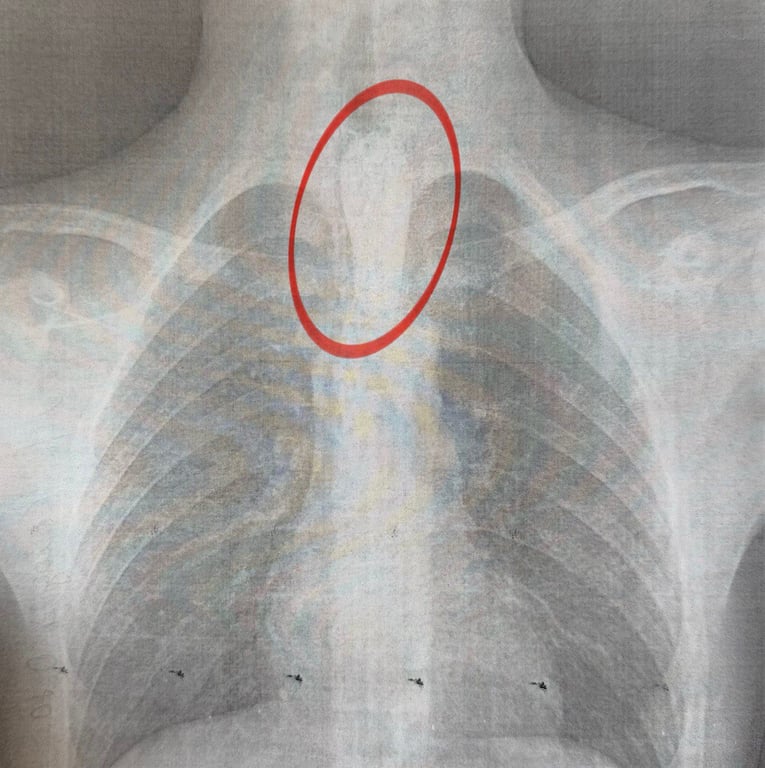

"Стравохід має природні звуження: на рівні шиї, біля аорти та на вході до шлунка. У цьому випадку шматок м'яса зупинився на другому звуженні. Слина постійно виробляється, але не може пройти далі, що викликає сильну слинотечу, відчуття стороннього тіла за грудиною і страх. Дитина не могла нормально дихати", — розповів торакальний хірург лікарні "Охматдит" Олександр Колодій.

Операція відбулася вночі — хлопця терміново доставили до операційної. Процедура тривала близько години: великий шматок м’яса видаляли обережно, щоб не пошкодити стінки стравоходу. Операція пройшла успішно, і хлопця вже виписали додому.